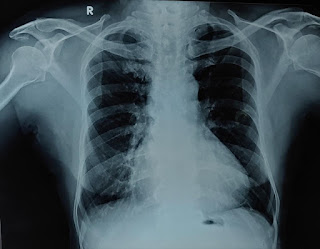

65 YEAR OLD MALE FARMER WITH METABOLIC SYNDROME (DM, HTN, CAD-HF, CKD)

A 65-year-old male from Chityal Farmer by occupation was brought to ER with complaints of bilateral pedal edema, and shortness of breath since 15 days.

Since 15 days he has complaints of bilateral pedal edema extending up to the shin of the tibia, and increased shortness of breath grade 3-4 associated with orthopnea & PND.

Acute on Chronic LVF ? secondary to CAD

Anemia ?secondary to CKD

K/c/o CKD since 2 years on MHD since 1 year